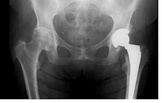

Złamanie biodra jest stanem cechującym się dużą śmiertelnością i chorobowością wśród chorych w podeszłym wieku. Zoptymalizowana płynoterapia śródoperacyjna może być korzystna w tej grupie chorych. Badano, czy śródoperacyjna płynoterapia monitorowana przy użyciu analizy konturu tętna w porównaniu ze standardowymi metodami u chorych znieczulanych podpajęczynówkowo, może przynieść korzyści w postaci skrócenia czasu do osiągnięcia stanu umożliwiającego wypis i zmniejszenia częstości występowania powikłań pooperacyjnych.

więcejPłynoterapia kontrolowana metodą LiDCO (Lithium Indicator Dilution Calibration) u chorych poddawanych alloplastyce stawu biodrowego w znieczuleniu podpajęczynówkowym.

Wybór techniki znieczulenia u osób poddawanych wymianie stawu biodrowego jest nadal dyskusyjny. Założeniem tego badania było udowodnienie, że znieczulenie ogólne niesie za sobą więcej korzyści w bezpośrednim okresie po znieczuleniu niż blokada rdzeniowa.

więcejCałkowite znieczulenie dożylne versus znieczulenie podpajęczynówkowe do zabiegu wymiany stawu biodrowego, kontrolowane badanie z randomizacją.